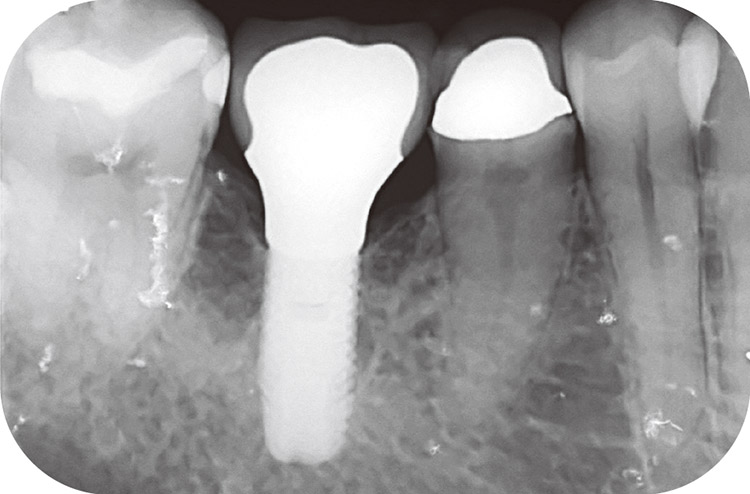

図14 6インプラントが埋入されている部位へのPMTC。

図15 6インプラント部位のデンタルX線画像。